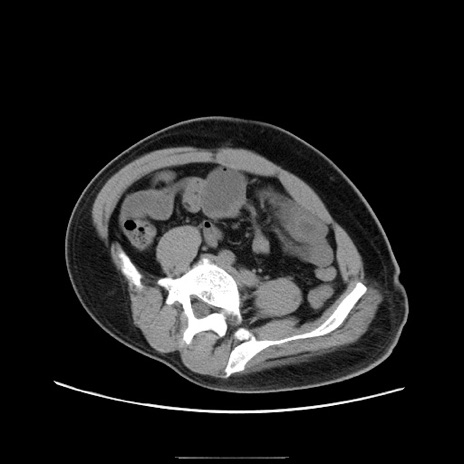

症例22(横断像)

【症例】50歳代男性

【主訴】腹痛

【現病歴】AVMからの被殻出血のため回復期リハ病棟入院中。 本日午後3時頃急に下腹部痛が出現した。

【既往歴】AVM、被殻出血、虫垂炎、高血圧

【身体所見】意識晴明、左半身不全麻痺、会話の理解は良好、36.5°C、腹部:膨隆、全体に板状硬、下腹部正中に圧痛点あり、反跳痛-、筋性防御不明、右下腹部にope scar

【データ】WBC 9400、CRP 0.06